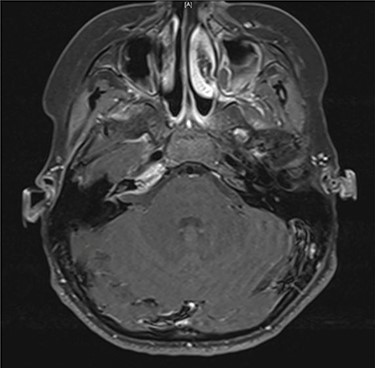

Serial MRIs were conducted following discharge. MRI at 1 month showed a contrast-enhancing mass in the right internal auditory canal with enhancement of the right petrous apex and associated labyrinthitis. An MRI at 2 months showed persistence of the lesion, whereas computed tomography (CT) showed new osseous erosion and irregular lucency within the posterior cortex of the petrous apex (Figs 1 and 2). Given the patient’s hearing loss, persistence of the lesion and concern for neoplasm, surgical intervention was recommended to the family. Surgery was initially deferred, and serial imaging was recommended. The facial nerve palsy resolved and patient was followed closely as outpatient with family reluctant to pursue surgical intervention. However, repeat imaging at 4 months after the initial encounter demonstrated persistence of the lesion, and the family consented to surgery.

Axial contrast-enhanced T1-weighted image taken 3 months after admission shows enhancement within the right petrous apex and anterior aspect of the internal auditory canal.